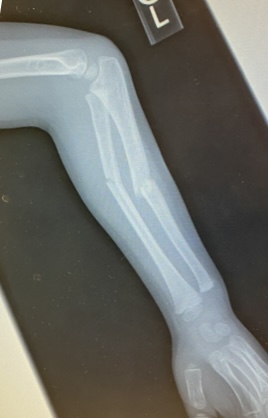

Oliver's Second Broken Arm

I feel like I'm writing the same post that I did 7 months ago, but here we are. Oliver was playing outside at summer camp and was running fast. Another kid's ball rolled in front of him, he tripped on it, and flipped over the top of it. As soon as I saw his arm, I knew that it was broken. I immediately called Riley, knowing that he would probably be able to take him to get it looked at faster than I could get a sub to cover for me. Riley's reaction was something to the tune of "Are you @#$%ing kidding me?' So after a visit to the Clay Center ER followed by an appointment at Orthopedics, it was determined that he broke his arm (again!) and would require surgery (again!). Now remember, he literally just had the pin removed from his last surgery at the end of last month.